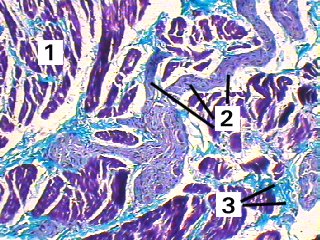

A low magnification of the nerve components of the heart.

Fig 047-003 1. Heart muscle

2. Nerve fibres

3. Endomysium